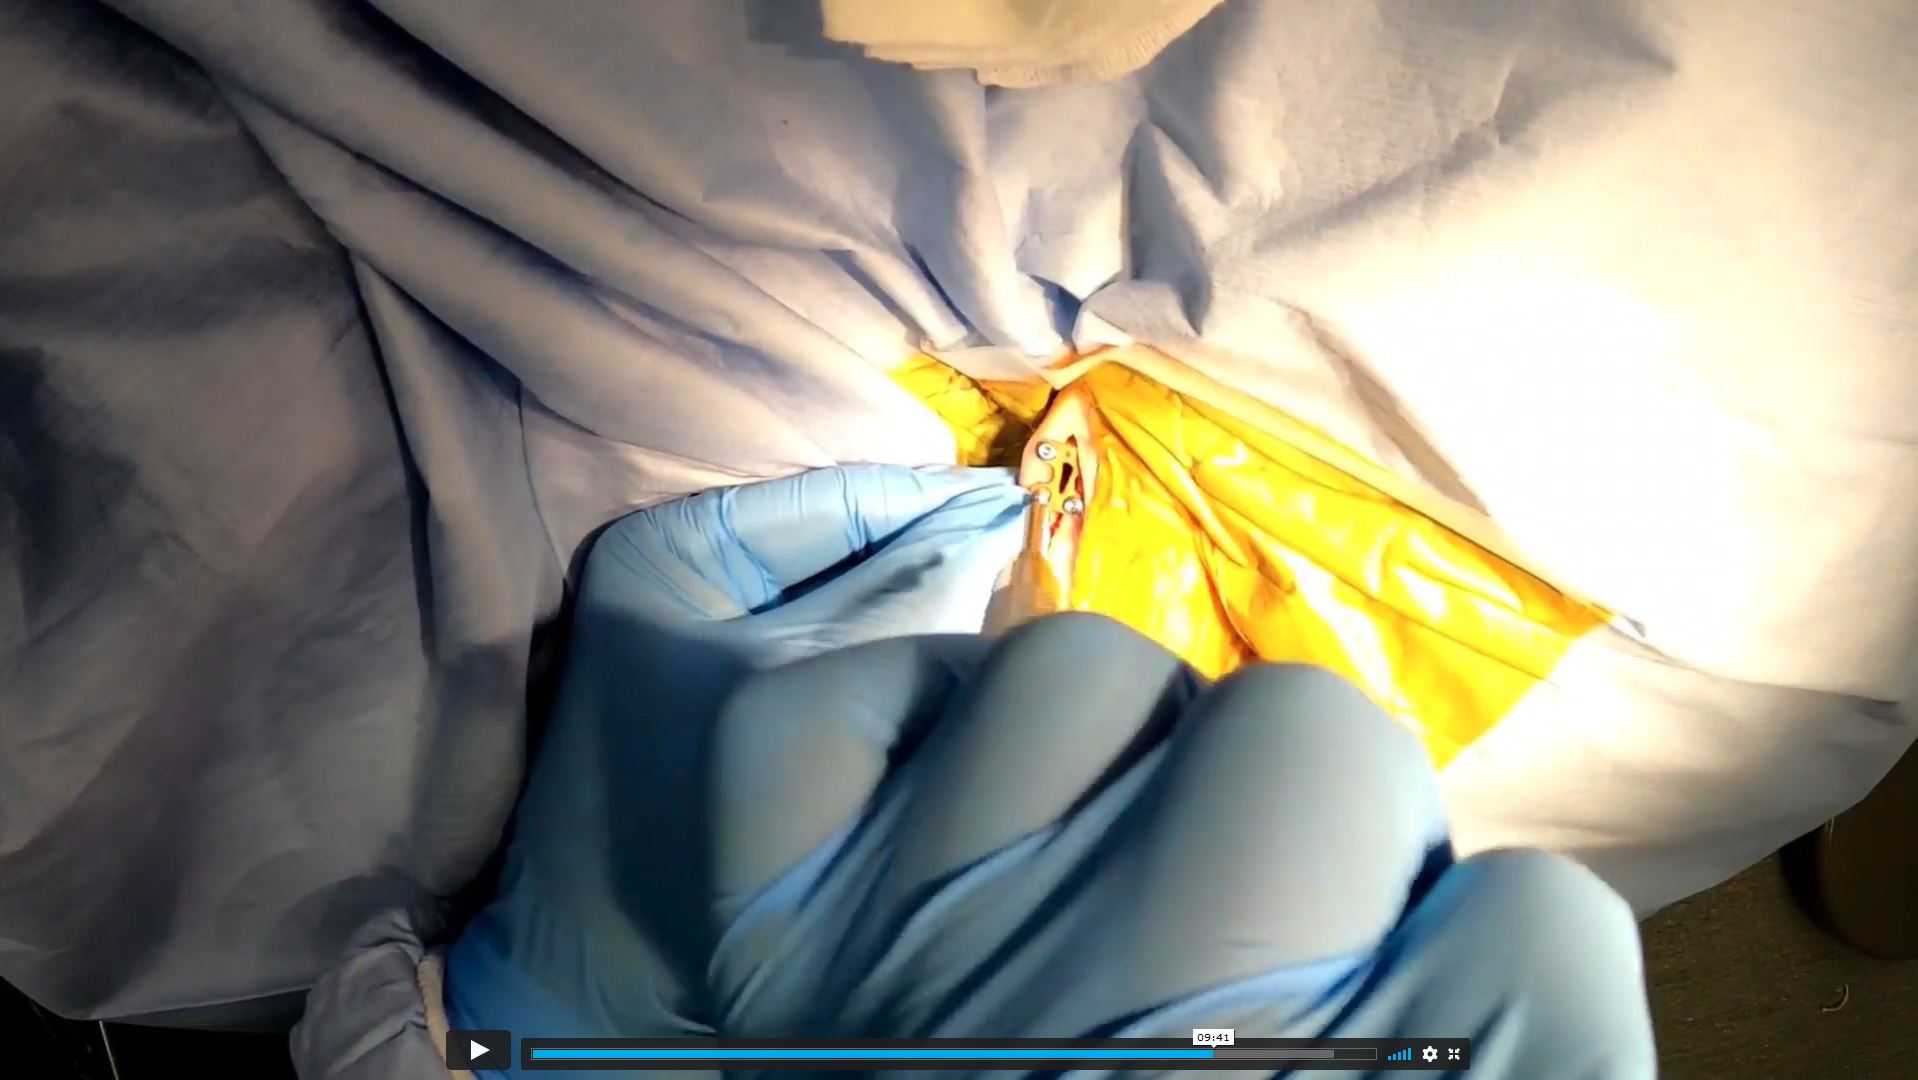

The sole distinction between this online course and a traditional wet-lab experience is the practical component. While this course provides an in-depth, real-time surgery demonstration with live commentary from Dr. Schmokel, participants are required to practice on cadavers independently.

11 Surgery